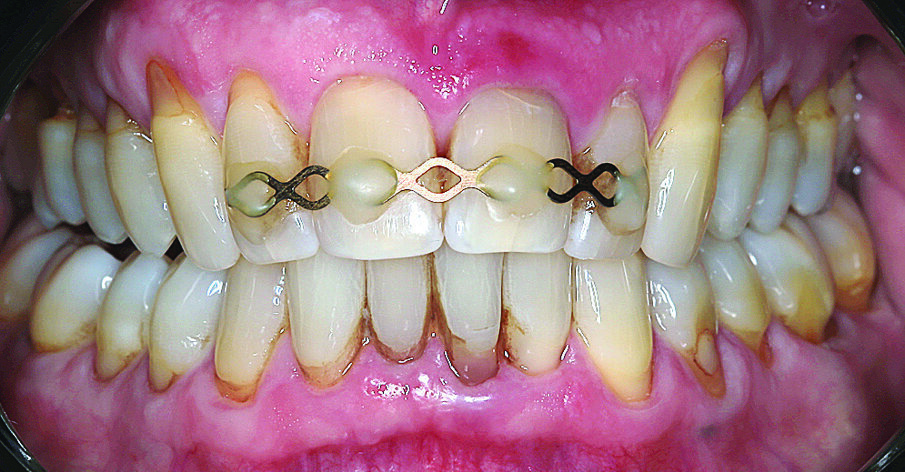

Budući da se to nije moglo isključiti za zub 21, u narednim posjetima provedeno je endodontsko liječenje s naknadnim punjenjem korijenskog kanala s MTA-om do pukotine (Slika 3.). Budući da je pacijent izrazio želju da se ne narušava estetika, za splintiranje je upotrijebljena palatinalna udlaga od PMMA-e (Slika 4.). Nakon tri mjeseca uočena je sve veća promjena boje zuba 21 i perzistentna pomičnost II. stupnja (Slika 5.). Nakon detaljnog informiranja o raznim mogućnostima liječenja kliničar i pacijent donijeli su odluku o implantoprotetskoj terapiji. CBCT snimljen tijekom planiranja terapije (Slika 6.), pokazao je blizak odnos prema vestibularnoj koštanoj lameli (položaj korijena I. razreda)14. Da bi se stvorio stabilan profil mekog i tvrdog tkiva i pacijentu što prije osigurao dobar estetski rezultat, kliničar se odlučio na imedijatnu implantaciju uz primjenu socket shield tehnike.

Slika 4. Splintiranje s pomoću udlage od PMMA-e palatinalne strane